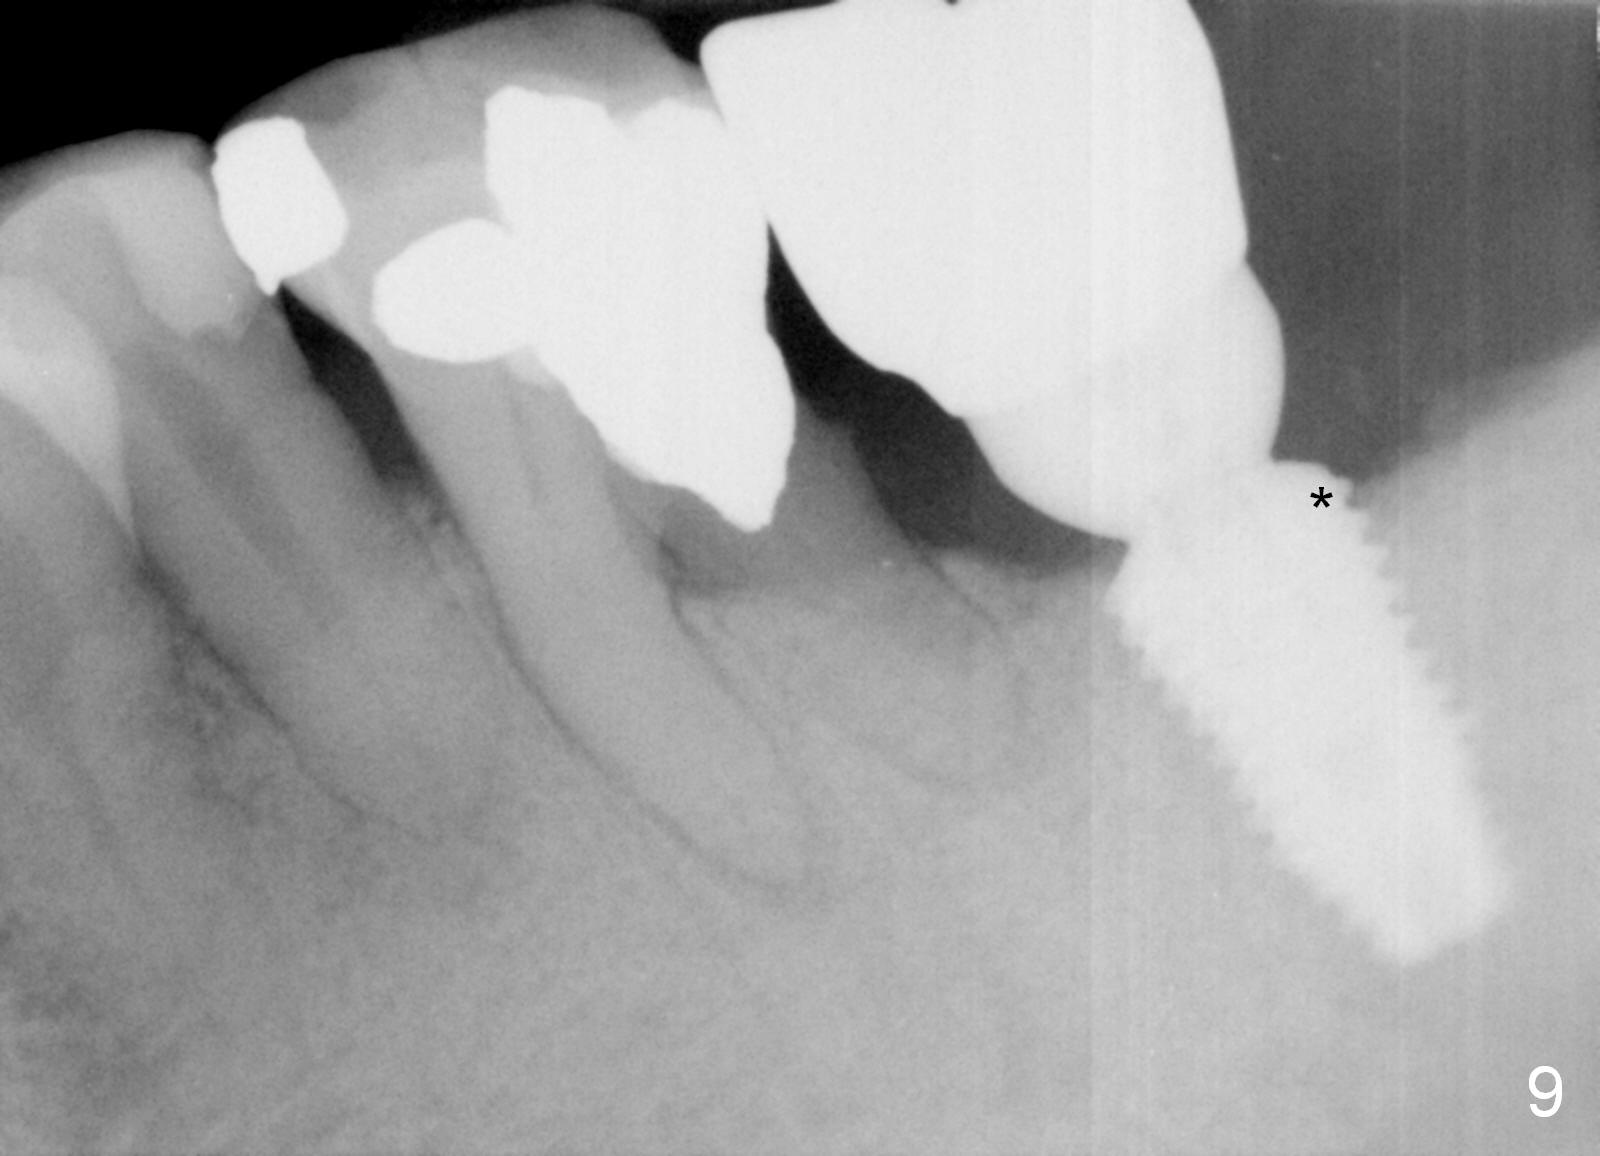

Eight months post cementation, the patient is pleased to let us know that he can chew peanuts with the implant crown (Fig.9) and asks for a 2nd implant.